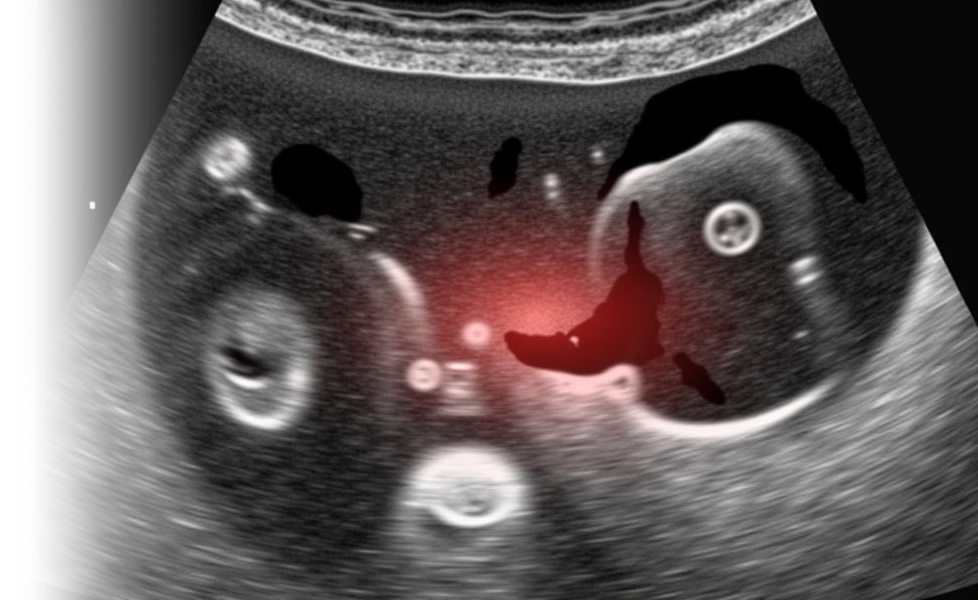

УЗИ брюшной полости – ультразвуковая комплексная диагностика состояния органов брюшной полости (включая печень, желчный пузырь, поджелудочную железу и селезенку).

В рамках данного исследования проводится оценка расположения, формы, контуров, анатомического строения, размеров, структуры и эхогенности органов, а также оценка сосудистого рисунка. Важным аспектом является выявление прямых и косвенных признаков опухолевого и неопухолевого поражения, а также оценка влияния окружающих тканей, органов и структур.

Исследование проводится с использованием специального ультразвукового аппарата, который позволяет врачу получить изображение внутренних органов пациента. Процедура безопасна и неинвазивна, что делает ее доступной для широкого круга пациентов.